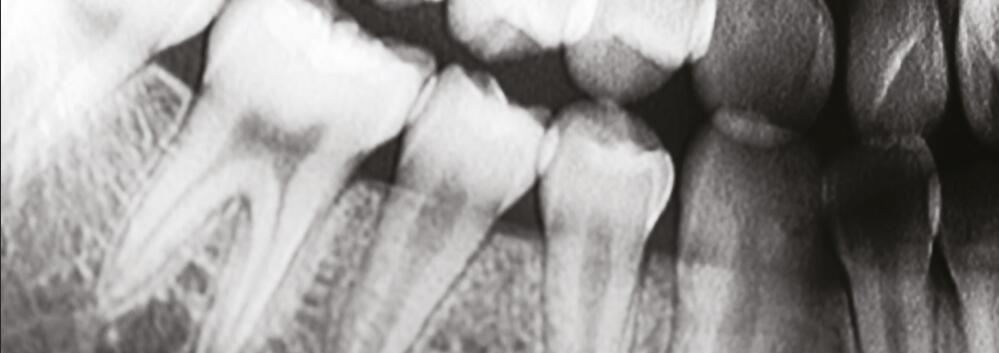

針狀碘化銫閃爍體的掃描電鏡圖像:針狀晶體具有限光作用,能夠有效降低光的散射,進一步提高空間分辨率